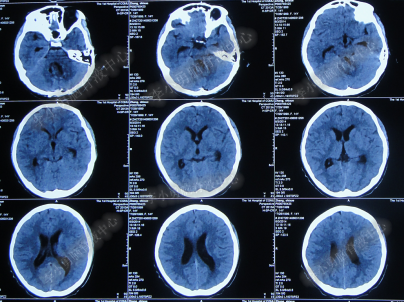

脑室外引流术后9天内,脑积水仍没有得到控制(图-12、图-13、图-14),且脑脊液仍有细菌。

图-12:2014年6月28日头部CT

图-13:2014年6月30日头部CT

图-14:2014年7月3日头部CT